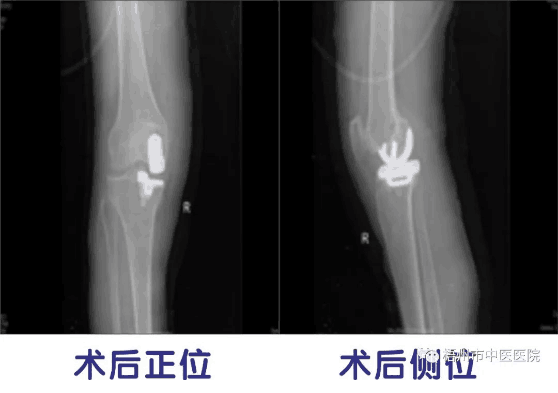

大骨科主任邓振中主任医师及其医疗团队经过反复讨论,为王某制定了“右膝关节单髁置换术”的手术方案,即仅对病变的内侧胫股间室进行表面置换,保留全部的交叉韧带和其余间室的软骨面,取得预期效果。患者术后第二天可自由上落楼梯行走。

据邓主任介绍,随着手术技术的成熟发展,使得膝关节单髁置换术的临床效果效果大大提高。与全膝关节置换术比较,单髁置换手术时间短、创伤小、出血少、保留自身骨量多、术后关节活动度大,并发症少,术后关节功能更接近生理状态,成为了膝关节骨性疾病病人的福音。